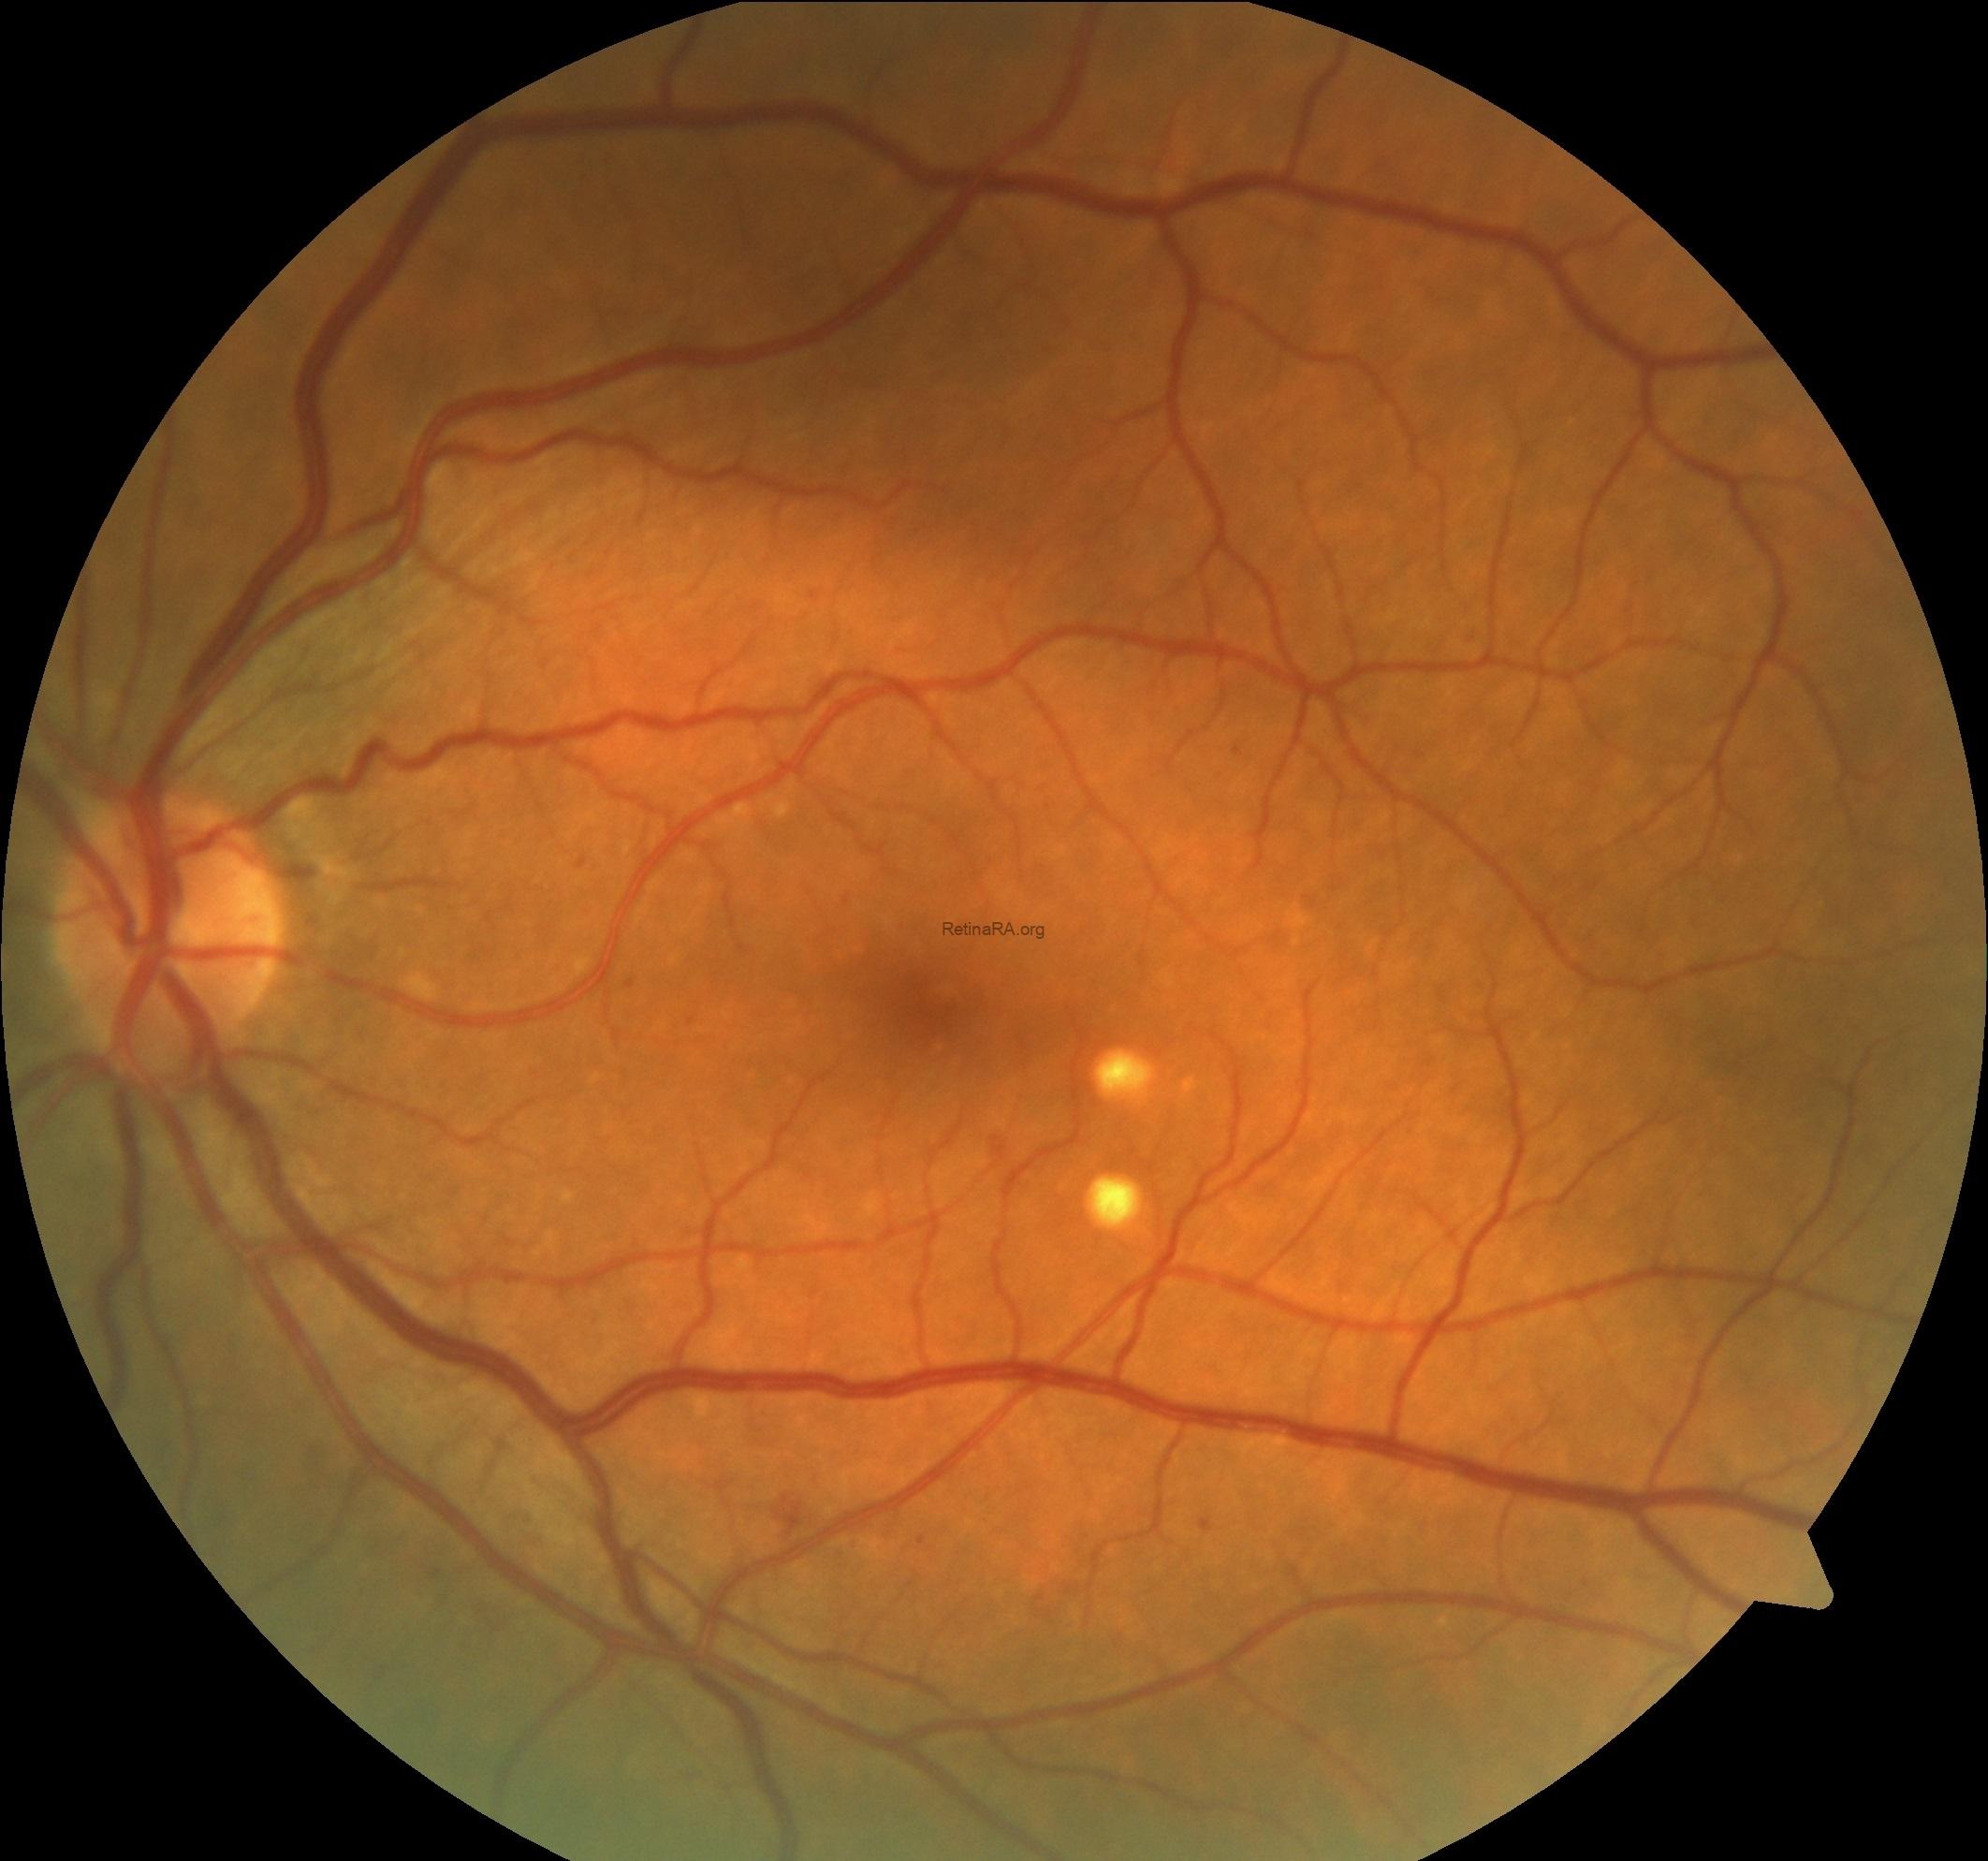

Fundus images of both eyes showed diabetic microaneurysms and a few yellow large drusen (

>125 μm) in the macula.